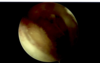

Performed comprehensive diagnostic arthroscopy. I evaluated the gutters for loose body I did not document visualization of the posterior compartment nor the medial meniscus tear. I did characterize the medial meniscal tear of absent any unstable flaps and did not warrant meniscal debridement. I did identify significant stenotic synovitis throughout the joint which underwent a synovectomy I also found a small areas of loose body that was less than 5 mm which I felt was broken up loose bodies. Had significant gapping in the lateral compartment which of poor performance of serial debridements to see if I can retrieve any loose bodies posteriorly however I did not place a trocar into the notch posteriorly to exclude any loose bodies there.

Performed arthroscopic synovectomy using a rotary shaver. In the suprapatellar pouch did not find numerous small loose bodies did not feel criteria to code as a loose body.

The medial compartment I did not identify an abnormal meniscus, I did see unstable cartilage flaps in the medial femoral condyle that elected to perform a chondroplasty using a rotary shaver.